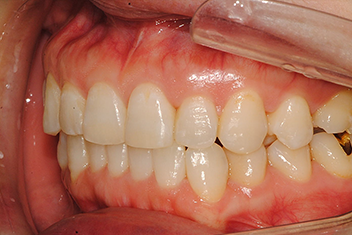

앞니 돌출 해소 케이스1

치료 기간16개월

심한 앞니 돌출을 투명교정으로 점진적으로 개선